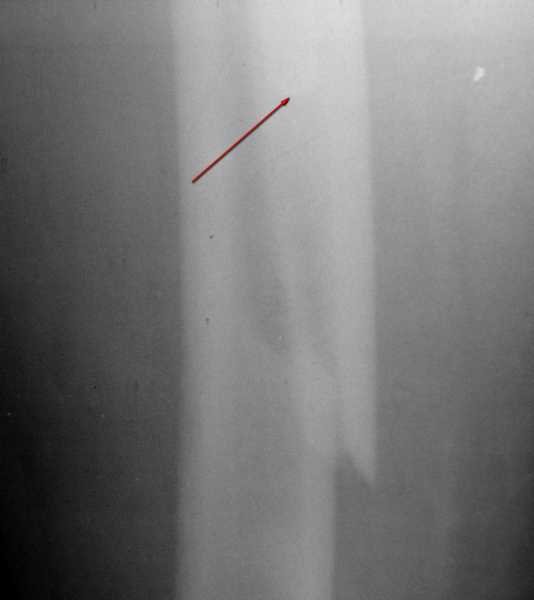

Вот фрагменты этих снимков с более различимыми областями интереса.

Насчет интраоперационной оценки стабильности - не уверен, что на не стоит полагаться, поскольку, похоже, цемент остается неплохо "прилипшим" к латеральной стенке костной трубки. То есть во время операции нестабильности не будет, но вот для последующей ходьбы...

Видимо, тут надо добиваться точной репозиции этой спирали вдоль протеза, чтобы воссоздать ложе для ножки.